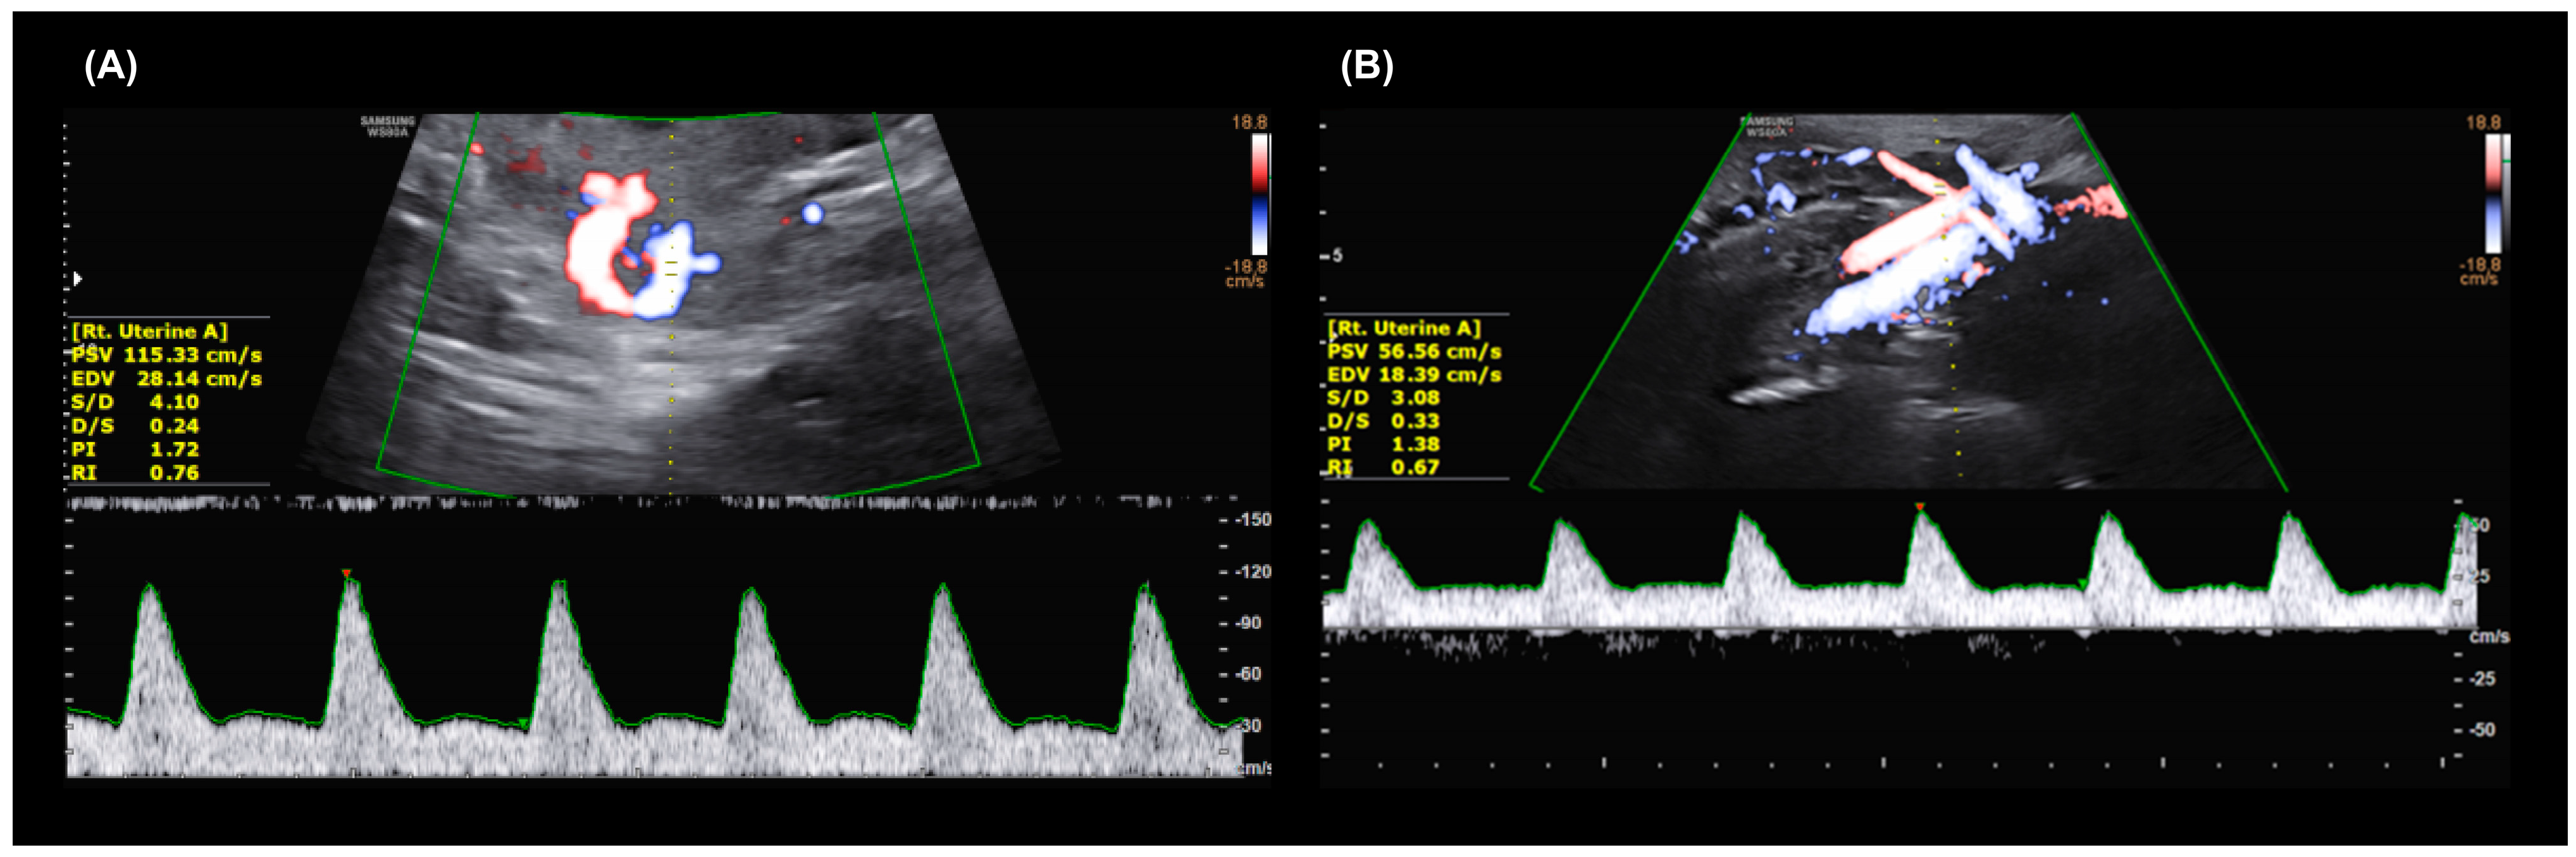

2.2. Maternal Serum Markers and Sonographic Procedures